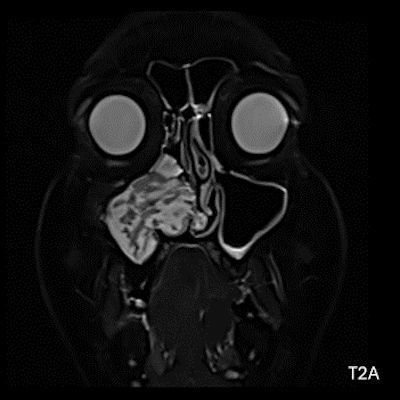

- A) Koronal T2 ağırlıklı görüntülerde sol maksiller sinüs lümenini dolduran, belirgin ‘convoluted’ (karmaşık-kıvrımlı) serebriform patern sergileyen lezyon (oklar), kontrastlı seride heterojen ve yoğun kontrastlanma göstermektedir (oklar). Perfüzyon incelemesinde pedinkülünde perfüzyon artışı gösterdiği, diğer kontrastlanan segmentlerin nispeten hipoperfüze olduğu görülmektedir (ok).

- MR incelemesinde sinonazal inverted papilloma tipik olarak T2 ve post-kontrast T1 serilerde ‘convoluted’ serebriform paternde heterojen sinyal ve kontrastlanma gösteren, pedinküler orijininde daha belirgin perfüzyon artışı sergileyen, genellikle difüzyon kısıtlaması izlenmeyen ve komşu sinüs duvarlarında ekspansiyona bağlı remodelinge yol açabilen benign ancak lokal agresif karakterde bir yumuşak doku kitlesi olarak izlenir.